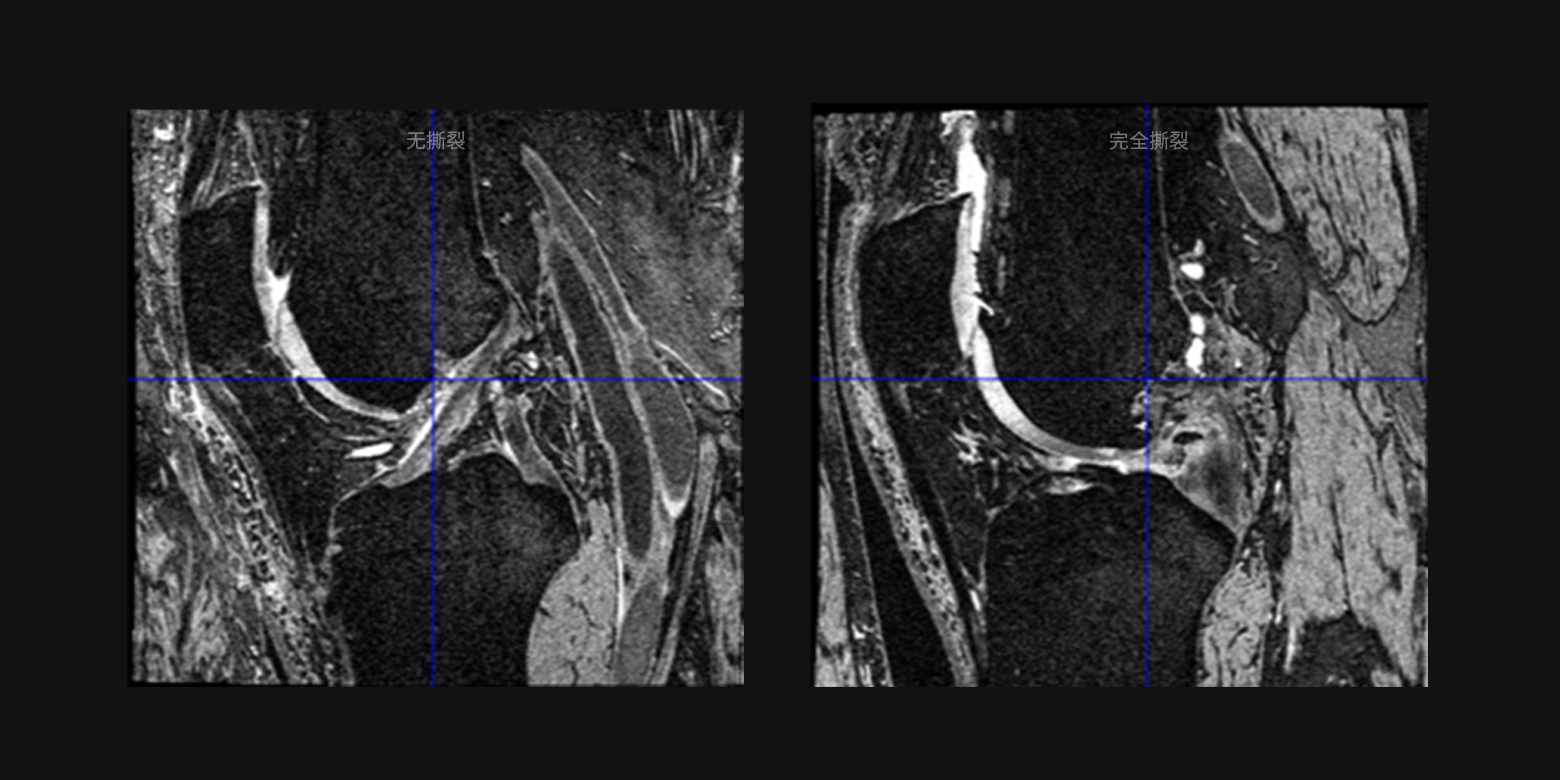

病灶良恶性鉴别与疾病分级

基于对复杂医学诊断要素的学习,支持多种病灶的良恶性鉴别或病情分级,例如十字韧带撕裂分级、肺结节良恶性鉴别等,满足疾病大范围筛查、分级诊疗等多种场景需求。

病灶良恶性鉴别与疾病分级

基于对复杂医学诊断要素的学习,支持多种病灶的良恶性鉴别或病情分级,例如十字韧带撕裂分级、肺结节良恶性鉴别等,满足疾病大范围筛查、分级诊疗等多种场景需求。